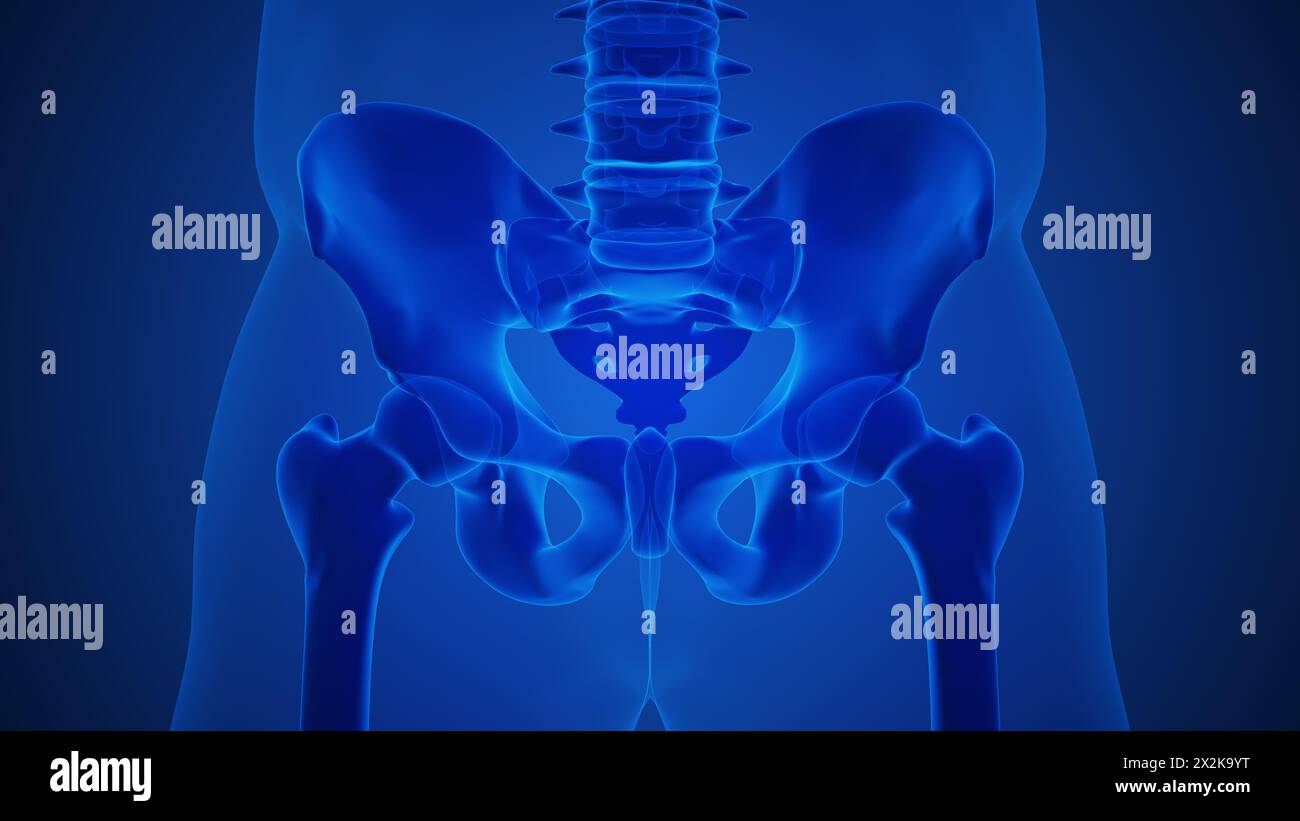

Anatomy concept of an arthritic sacroiliac joint Stock Photohttps://www.alamy.com/image-license-details/?v=1https://www.alamy.com/anatomy-concept-of-an-arthritic-sacroiliac-joint-image604017116.html

Anatomy concept of an arthritic sacroiliac joint Stock Photohttps://www.alamy.com/image-license-details/?v=1https://www.alamy.com/anatomy-concept-of-an-arthritic-sacroiliac-joint-image604017116.htmlRF2X2K9YT–Anatomy concept of an arthritic sacroiliac joint